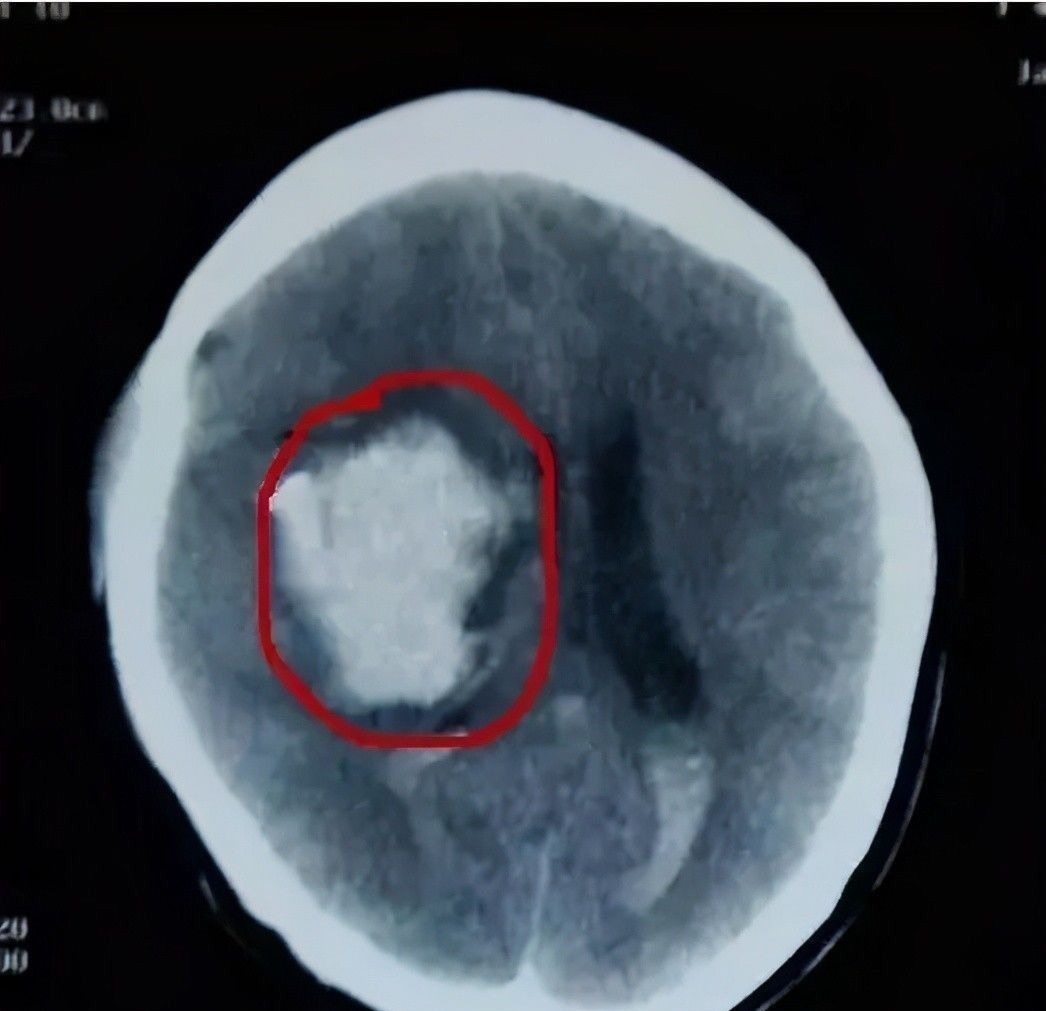

如若是关乎到孩子的脑颅内神经以及其他一些比较关键的部位的话,那也一定要及时就医,避免耽误了治疗。